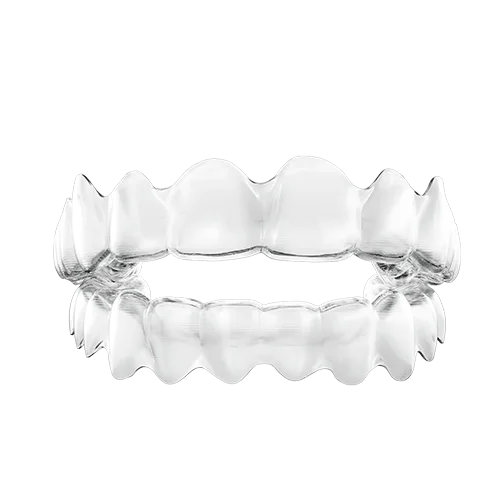

Şeffaf Plaklar- Bu tedavi tekniğine halk arasında telsiz ortodonti de denmektedir. Estetik beklentisi yüksek olan hastalar için ideal bir seçenektir. Şeffaf apareylerin en çok tercih edilen markası Invisalign’dır (Şekil 15). Invisalign’la hiç diş teli takmadan ortodontik tedavi yaptırabilirsiniz. Plakları istediğiniz zaman takıp, istediğiniz zaman çıkartabildiğiniz için günlük hayatta çok konforlu bir tedavi seçeneğidir.